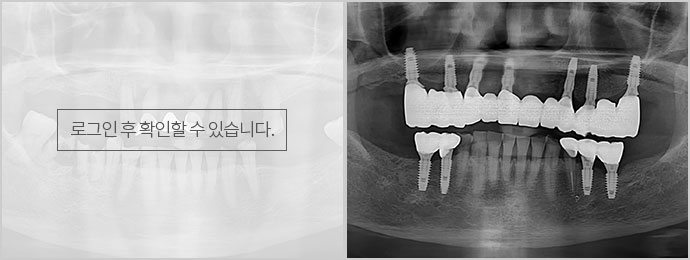

상록제일치과의 UV 임플란트는 생활성 자외선 광촉매 표면처리를 통해 친수성이 우수하고 보철물의 노화를 막아 골밀도가 좋지 않은 경우에도 생체활성도를 높여 견고한 골재생뿐만 아니라 치료기간을 단축할 수 있는 장점이 있습니다.